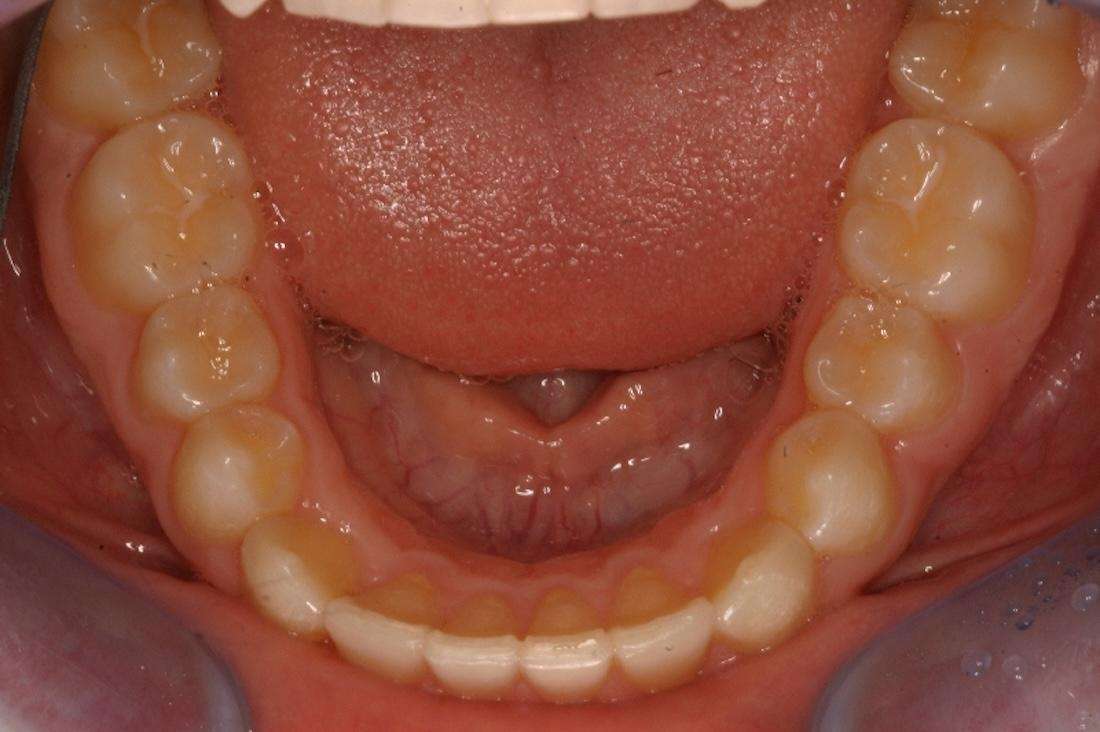

Before

After